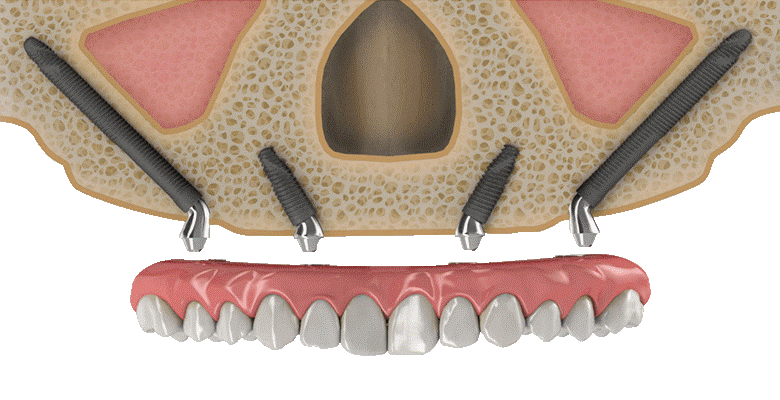

All-on-6 Dental Implants:

All-on-6 dental implants are a premium full-mouth rehabilitation solution that uses six strategically placed titanium implants to support a complete arch of fixed teeth. This advanced treatment provides superior strength, stability, and long-term support for patients with multiple missing teeth or complete tooth loss. All-on-6 implants restore natural chewing ability, speech, facial aesthetics, and smile confidence while offering a comfortable and secure alternative to removable dentures. The additional implant support improves durability and bite force, making it an ideal solution for long-lasting smile restoration. With advanced digital planning and precision techniques, All-on-6 implants deliver natural-looking and highly successful results.

Implant Supported Dentures:

Implant supported dentures are a modern and secure solution for replacing multiple missing teeth using dental implants for added stability and comfort. Unlike traditional removable dentures, these dentures are firmly attached to implants placed in the jawbone, preventing slipping or movement while eating and speaking. Implant supported dentures improve chewing efficiency, speech clarity, facial appearance, and overall confidence. They also help preserve jawbone structure and provide a more natural feel compared to conventional dentures. This treatment is ideal for patients looking for a comfortable, long-lasting, and reliable tooth replacement solution with enhanced function and aesthetics.